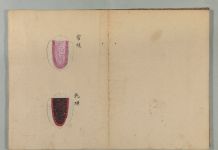

經曰:診脈之道,觀人勇怯,

肌肉皮膚,能知其情,以為診法也。

人之色,白不及黑,嫩不及蒼,薄不及厚。

素問に基づいた望診と脈診で

人を診ていくことの大事さを説いております。